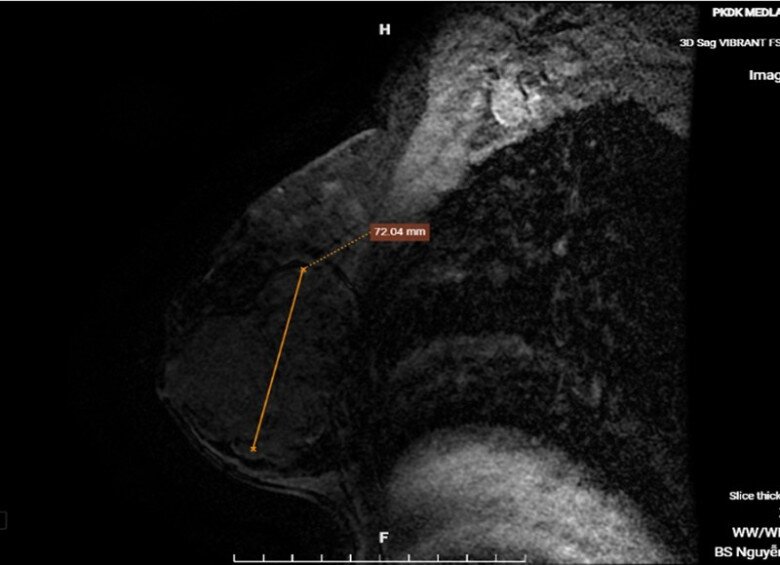

Kết quả chụp MRI vú cho hình ảnh khối u tuyến vú phải, bờ đa cung với đường kính lên tới 72mm. Ảnh: BSCC.

Kết quả chụp MRI vú cho thấy, có hình ảnh nghi ngờ khối u ác tính khi bờ đa cung ngấm thuốc dạng type I, nên các bác sĩ hướng đến u xơ tuyến vú. Do nghi ngờ ung thư, bệnh nhân được thực hiện sinh thiết để hỗ trợ chẩn đoán. Kết quả sinh thiết của bệnh nhân và chẩn đoán xác định, chị H mắc u xơ tuyến vú.

Ngay sau đó, ê kíp bác sĩ đã thực hiện phẫu thuật và lấy ra thành công khối u khủng có kích thước 10x7x5,5cm. Tiếp tục cắt lấy mô u vừa được phẫu thuật để làm sinh thiết, kết quả khiến chị H thở phào nhẹ nhõm và mừng rơi nước mắt khi đây không phải khối u ác tính.